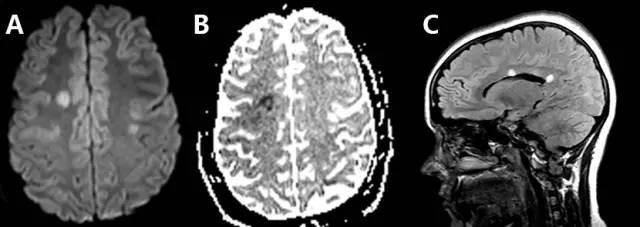

CADASIL的主要特点是双侧前颞叶白质和外囊受累,且急性病变多表现为弥散受限(图1)。

图1 一例40岁的男性患者,因意志力缺乏和左侧面部下垂而急诊就医。MRI显示其双侧半卵圆中心和放射冠部位有多灶性的弥散受限和增强改变(A:DWI,B:ADC),并伴有双侧脑室周围白质、双侧前颞叶部位相关的T2高信号病灶(C&D:T2WI)。Notch 3基因突变证实了其为CADASIL。